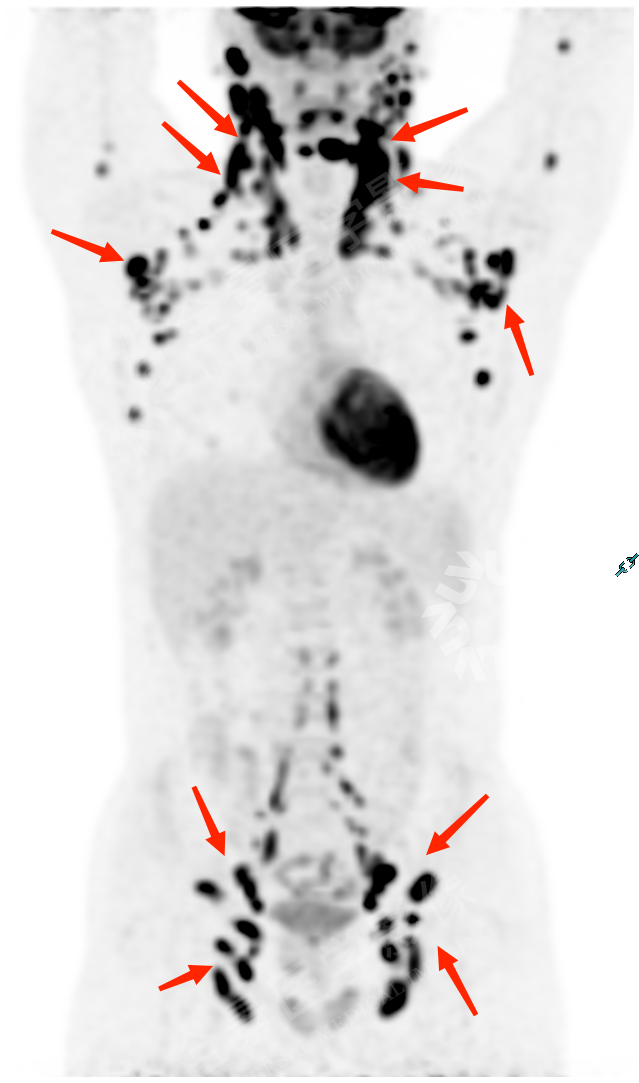

化疗 4 周期后,再次 PET/CT 复查:

PET/CT 复查显示:原全身多发增大淋巴结此次复查明显缩小,大部分已消退,FDG 代谢未见异常,考虑治疗后明显好转。

经过规范化治疗,小瑞病情得到明显的好转。也正因为 PET/CT 检查, 给小瑞的治疗过程提供了宝贵的信息。